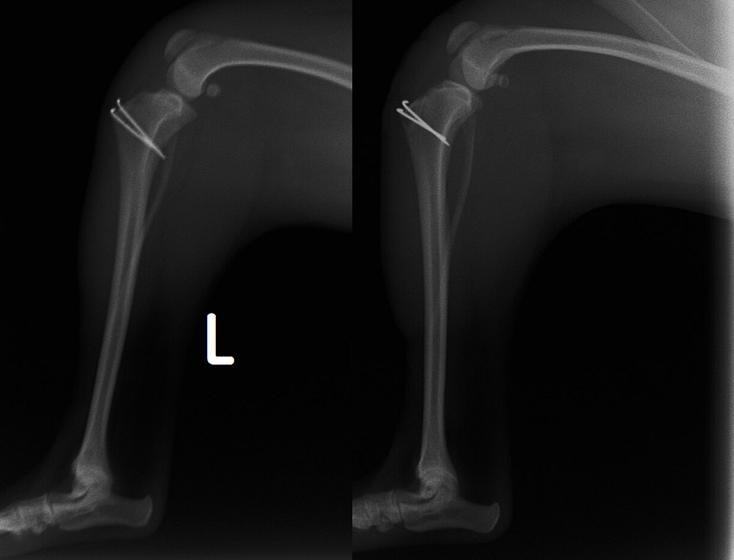

■ 症例22 ポメラニアン 1歳5か月 去勢雄

左後肢の挙上を主訴に来院した。整形学的検査、レントゲン検査より左右の膝蓋骨脱臼(左GradeⅡ〜Ⅲ、右Grade Ⅱ)を認めた。また、脛骨の前方引き出し試験の際に、引き出し兆候は認められないものの、疼痛が認められたため、前十字靭帯の損傷が疑われた。術中における、目視および関節内の操作によって、前十字靭帯の損傷や過伸展といった異常が認められなかったため、膝蓋骨脱臼の整復のみ実施した。手術手技は縫工筋及び内側広筋の解放、脛骨粗面の外側転位、滑車ブロック形造溝術、内外側関節包の縫縮を実施した。本症例は跛行もなく経過良好である。しかし、頸骨高平部の角度(TPA)が 右26.2°、左24.9°であり、解剖学的に前十字靭帯損傷のリスクが高いことから今後の経過に注意が必要である。